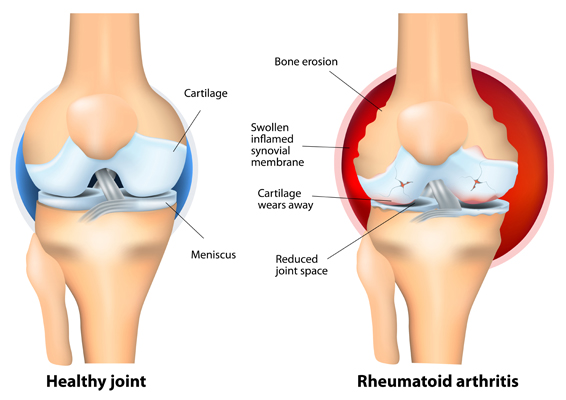

To understand how RA affects your body, it’s helpful to know a little about your joints.

Joints are places where bones meet. Bones, muscles, ligaments and tendons work together so you can twist, bend and move about.

The ends of your bones are covered in a thin layer of cartilage. It acts like a slippery cushion absorbing shock and helping your joint move smoothly.

The joint is wrapped inside a tough capsule filled with synovial fluid. This fluid lubricates and nourishes the cartilage and other structures in the joint.

When you have RA, and the immune system targets your joints, it causes a build-up of synovial fluid and inflammation of the tissues that line the joint (synovial membrane). This causes pain, heat and swelling.

Cartilage becomes brittle and breaks down. Because the cartilage no longer has a smooth surface, the joint becomes stiff and painful.

Ligaments, tendons and muscles surrounding the joint can also be affected, causing joints to become unstable.